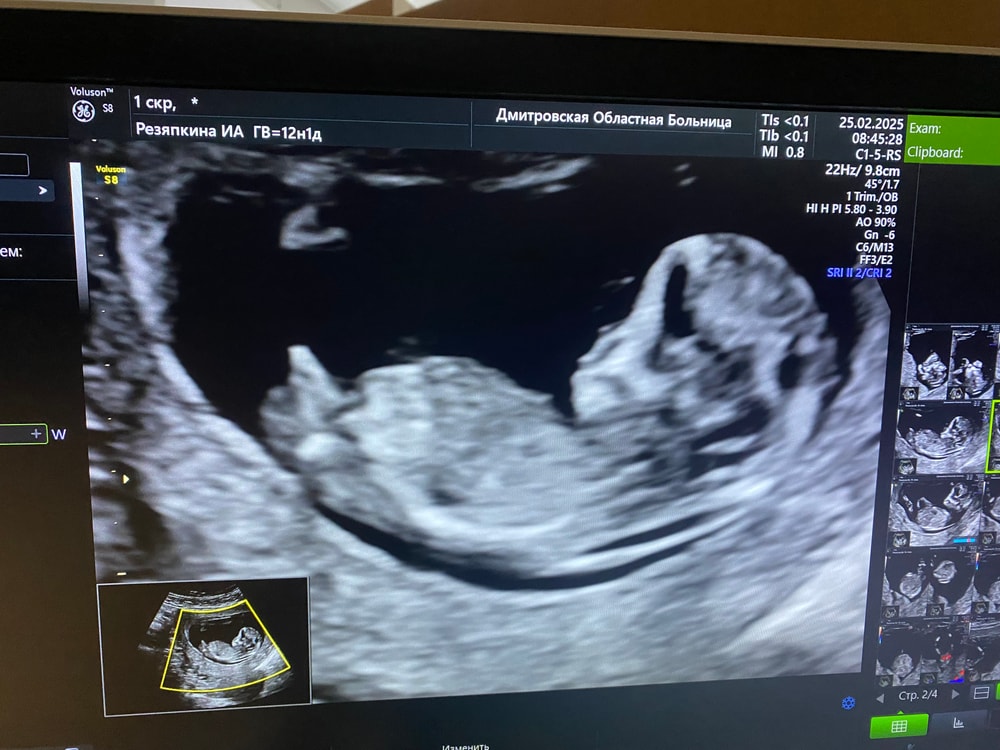

Мила , нет, только общий вид. Есть фото с 1 скрининга, там как бы вверх торчит... Изображение

Ирина Резяпкина, Фото малыша в 12+6 и в 16 недель УЗИ | форум Babyblog у меня у сына вот так торчало в 12,6, у Вас такого не вижу

Ирина Резяпкина, возможно на этом первом фото, это не половой бугорок торчит, а кость бедренная так получилась

Ирина Резяпкина, это явно не половой бугорок, а нога